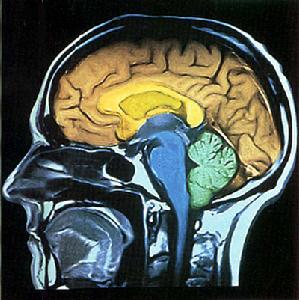

在手術中,醫生將把波爾的大腦作為手術目標而不是她的胃。腦深層電刺激已經證明在治療如帕金森和癲癇症之類的神經類疾病頗為成功。醫生們相信這種程式對如強迫症和抑鬱症等行為問題有一定療效,現在又燃起了用它來對抗肥胖的希望。西維吉尼亞大學神經外科醫生們在食品和藥物管理局的授權下開始研究腦深層電刺激對肥胖症的治療。西維吉尼亞大學神經外科主任朱利安·貝勒斯博士說:“手術並非針對超重人群,而是針對肥胖人群的。”他承認,目前美國三分之二的人是超重人群。他說:“記住,肥胖本身會減少你的壽命可能20年。肥胖與很多其他疾病有關:糖尿病、心臟病和其他疾病。所以,這是一個重要問題……。我們認為,既然我們可能比大多數人更了解一些病情,作為醫生我們的責任是了解大腦對肥胖的潛在影響。”

既然頭顱和大腦中沒有感受疼痛的接受體,波爾只需要局部麻醉。在整個手術中她是清醒的。她說:“我因為自己的清醒而感到興奮,我希望醒著,因為如果我醒著,我就知道手術要做什麼。”神經外科醫生麥可·奧和唐納德·懷汀在波爾的大腦兩半球通過一個不影響其他功能的組織通道鑽入約10厘米。在到達控制胃的視丘下部的地方,引入一根金屬絲,這根金屬絲最終將攜帶一個電脈。醫生打算藉此改變該區域自然產生的電量,讓波爾產生飽腹感。手術由電腦跟蹤,電腦可幫助手術找到引入電極的地方。麥可·奧說:“雖然現在這種科技我們用於減肥,但是,在不久的將來它肯定有更多套用可能性,將用於多種神經退行性疾病。”